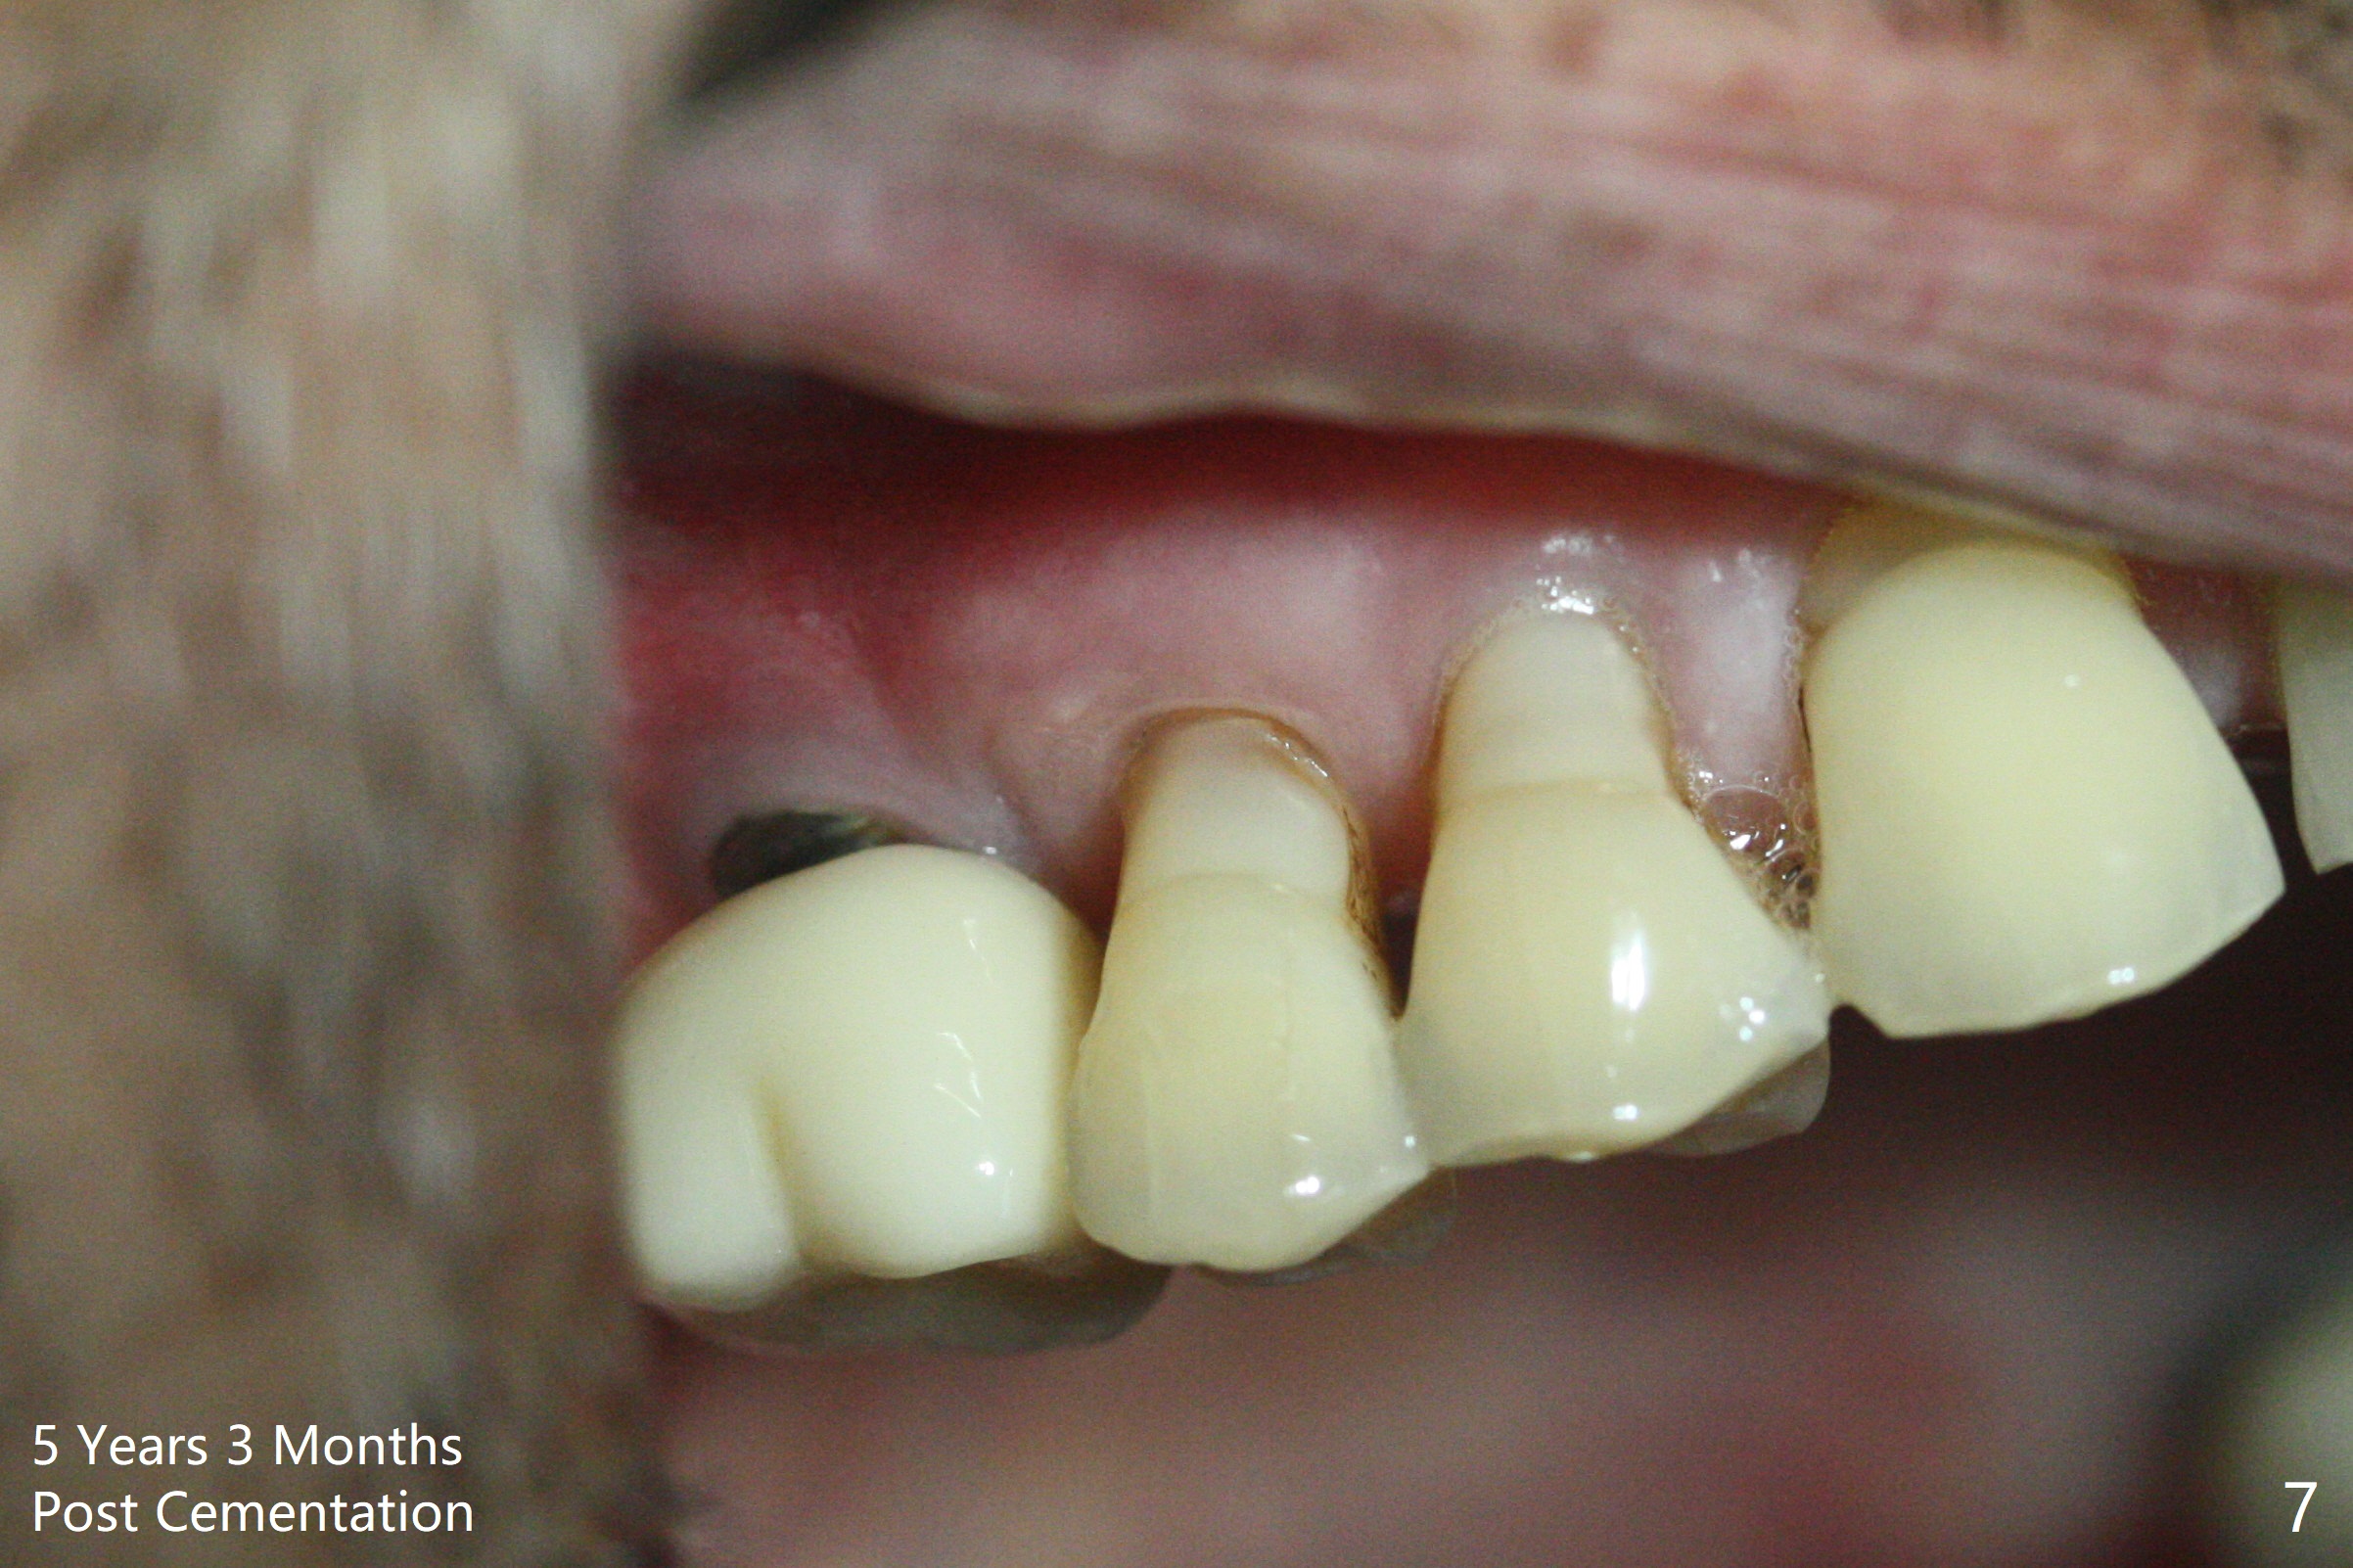

The implant is also found to have been placed buccal (Fig.6 B (CBCT 2 years 9 months post cementation)). In spite of one buccal thread exposure (Fig.8 I), there is no sign of periimplantitis 5 years 3 months post cementation, as related to good oral hygiene (Fig.7).